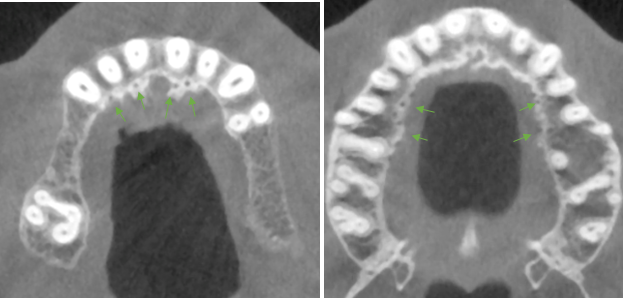

The data of 18 adolescents was described (7 males and 11 females). The age group ranged from 7 to 18 years (mean age=15.8 years). Eight cases presented at least 1 AC (44%) and a total of 15 ACs were identified, with only 3 cases showing an AC with a foramen width greater than 1mm (16.7%, 95% confidence interval [3.6%; 41.4%]) see Table 5 [Tab. 5] and Table 6 [Tab. 6]. The locations are not equally distributed. The most common sites are "left canine and lateral incisor" and "central incisors". Least likely sites are the right and left bicuspids. In (77.8%) the CS was measured to be ≥1 mm. The same number of left and right IOC in the sinus wall was documented for 17 adolescents (94.4%, 95% confidence interval [72.7%; 99.9%]). All 17 showed a symmetrical course of the canals (100% of 17, 95% confidence interval [80.5%; 100%]). The radiological findings are illustrated in Figure 3 [Fig. 3], Figure 4 [Fig. 4], Figure 5 [Fig. 5], Figure 6 [Fig. 6], Figure 7 [Fig. 7], Figure 8 [Fig. 8], Figure 9 [Fig. 9].

Figure 3: Example of accessory foramina in the axial view